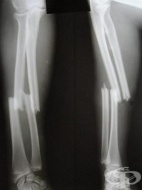

S52.9 Счупване на неуточнена част на костите на предмишницата

Заболявания

Счупванията на костите на предмишницата са едни от най-често срещаните. Около 25% от всички счупвани...